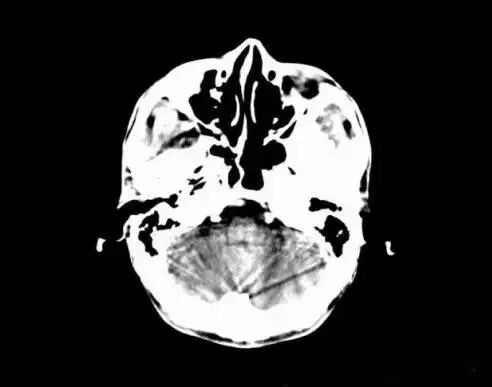

(運動偽影)

1、運動偽影

在掃描過程中,如果病人體位發(fā)生變化,可造成圖像數(shù)據(jù)排列紊亂。重建圖像結(jié)構(gòu)模糊,無法分辨。運動偽影又分為自主運動偽影和生理性運動偽影。

(1)自主運動是指那些患者可以控制的運動,如呼吸運動、體位移動等。

(2)生理性運動是隨機的,不能由患者自主控制,如心臟管搏動、胃腸蠕動等。